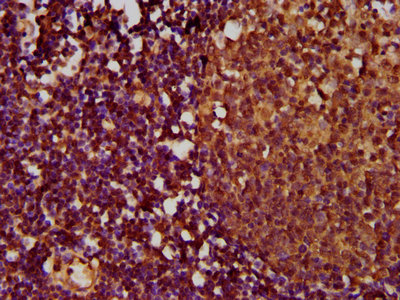

IHC image of CSB-PA023975LA01HU diluted at 1:500 and staining in paraffin-embedded human lymph node tissue performed on a Leica BondTM system. After dewaxing and hydration, antigen retrieval was mediated by high pressure in a citrate buffer (pH 6.0). Section was blocked with 10% normal goat serum 30min at RT. Then primary antibody (1% BSA) was incubated at 4°C overnight. The primary is detected by a biotinylated secondary antibody and visualized using an HRP conjugated SP system.